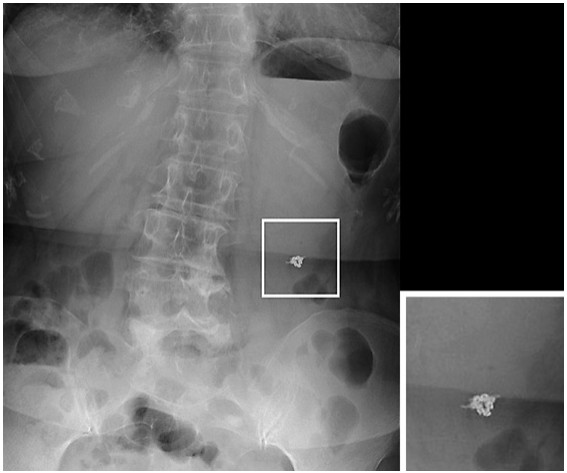

Methods: Twenty-five consecutive patients who underwent endoscopic treatment and whose artificial ulcer was closed using the SCCT were enrolled in this study. The technical success rate, number of clips for closure, procedure time, complication rate on the day of the procedure, clinical success rates on days 1 and 5, and incidence of severe stenosis of the gastrointestinal (GI) tract at 2 months after the procedure were evaluated.

Results: The median ulcer diameter was 20 mm. The tumor locations were the stomach (n = 19), jejunum (n = 1), and colon (n = 5). The technical success rate was 100% (25/25), and the rate of incomplete closure was 0% (0/25). Eight clips were needed on average. The median procedure time was 18 min (range 5–49 min). The complication rate was 0% (25/25). The clinical success rates on days 1 and 5 were 100% (19/19) and 100% (9/9), respectively. No patients presented stenosis as a late complication at 2 months after the procedure (0/25).